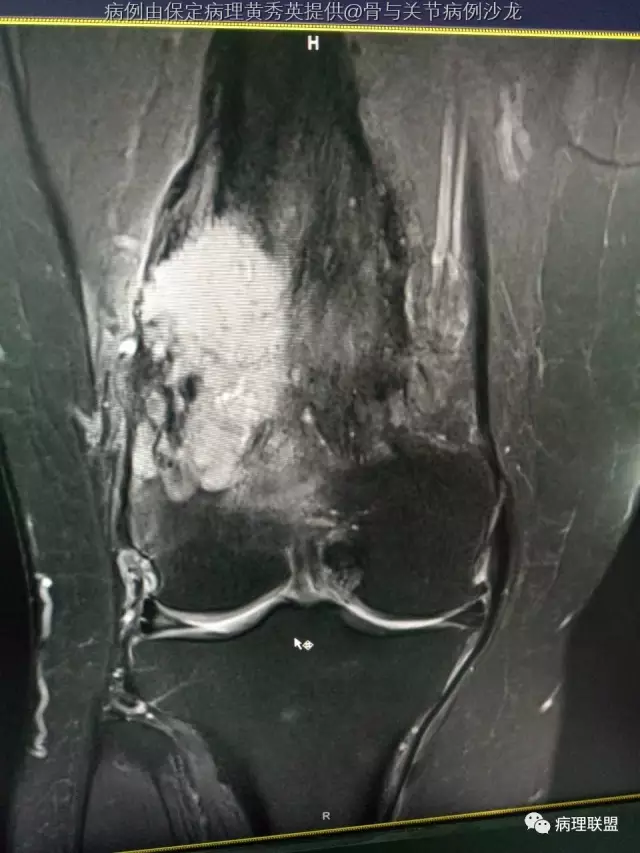

女67岁,股骨下端肿物约6cm,(病例由保定病理黄秀英提供,致谢!)